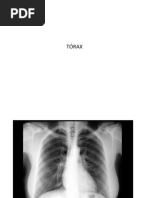

Esternn Costillas Vertebras dorsales Cartlagos costales